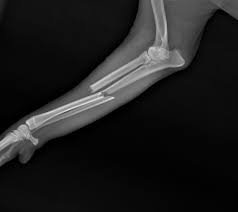

bone fracture dog

Broken bones can occur due to trauma such as:

• falls

• car accidents

• severe impacts

Fractures typically cause:

• severe pain

• swelling

• inability to bear weight

Fractures require immediate veterinary care.